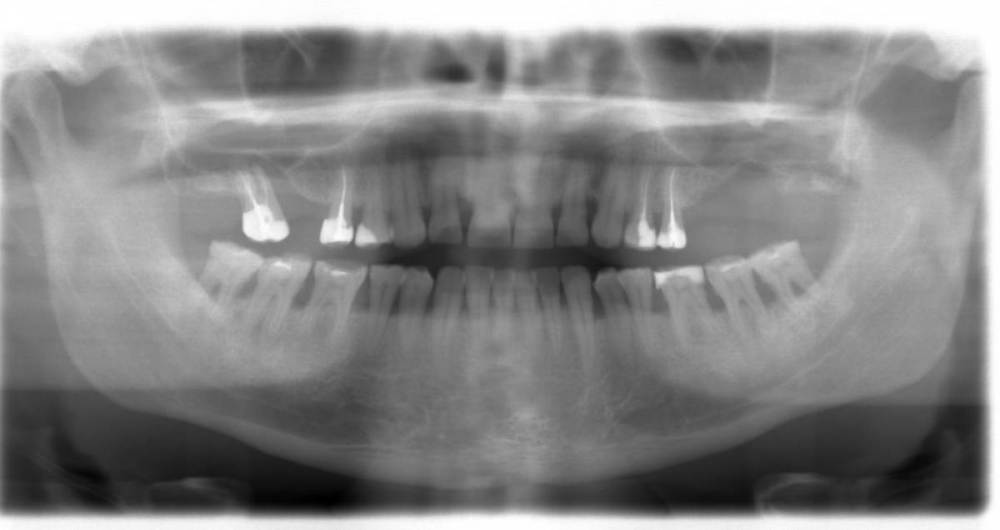

Chanba109 Опубликовано 26 марта, 2022 Поделиться Опубликовано 26 марта, 2022 Уважаемые специалисты, хочу поделиться своей ситуацией и спросить вашего совета. Ситуация следующая: мне 55 лет, до 2005 года терял зубы в верхней челюсти (был диагностирован парадонтоз, который сейчас стараюсь поддерживать в рамках). В 2005 году решил решить вопрос с восстановлением зубного ряда (съемным или несъемным). От имплантов отказался в пользу съемного протезирования из-за технических сложностей (тонкая кость верхней челюсти – требовался синус-лифтинг, снимок 2005 прилагаю) и общей высокой стоимости. Сделал выбор в пользу съемного гибкого нейлонового протеза Valplast, который ношу до настоящего времени, то есть уже 17 лет (фото протеза в настоящее время прилагаю). За это время никаких перебазировок, подгонок и т. п. с протезом не производилось, он сидит достаточно плотно, легко снимается и надевается, меня, в общем, полностью устраивал весь период использования. В настоящее время один из зубов (левая пятерка), за который держится протез, подлежит удалению (панорамный снимок, сделанный недавно, прилагаю). Встал вопрос о смене протеза или ином решении проблемы. У меня к вам следующие практические и теоретические, если так можно выразиться, вопросы: 1) Насколько критично идет уменьшение костной ткани в верхней челюсти? Насколько, по вашему мнению, этому способствовал гибкий нейлоновый протез или это, скорее, естественный процесс при парадонтозе? 2) Какой вариант протезирования с желательным бюджетом до 100 тыс. рублей (или немного выше) можете рекомендовать в моей ситуации? 3) Можете ли рекомендовать сделать еще один нейлоновый протез (или протез из аналогичных материалов - Acry Free или т. п.). 4) Надо ли перед протезированием удалять не только левую, но и правую пятерку (которая пока никак не беспокоит) или можно попробовать оставить ее? Панорамный_2005 год.tif Панорамный_2022 год.docx Ссылка на комментарий

Женька Опубликовано 26 марта, 2022 Поделиться Опубликовано 26 марта, 2022 Я бы убрал и слева и справа. Также обратить внимание на 1.2 зуб (боковой резец справа), возможно нужно полечить, под ОПТГ судить нельзя об этом. До 100 тысяч в нынешних реалиях это переделка протеза я думаю. Имплантация и синусы выйдут дороже. Касаемо первого вопроса опять же, по данным снимкам оценить это нельзя. Протез способствует в любом случае, но какая разница, если имплантация не вариант выбора для вас? Ссылка на комментарий

Chanba109 Опубликовано 28 марта, 2022 Автор Поделиться Опубликовано 28 марта, 2022 Спасибо за ответ. Имплантация в моем случае весьма небюджетна будет, это понятно. Но съемные протезы тоже разные бывают, какие можно рекомендовать при моем состоянии зубов и костной ткани (снимок МРТ 2022 года - выше в первом посте Евгения) ? Есть ли критические противопоказания к нейлоновому или т. п. гибкому протезу? Ссылка на комментарий